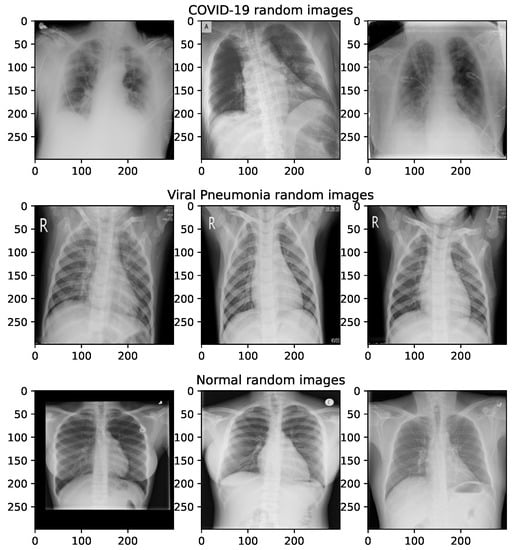

The majority of images for the dataset employed in this research is taken from the COVID-19 radiography database, which can be retreived from the following URL: https://www.kaggle.com/datasets/tawsifurrahman/covid19-radiography-database (accessed on 25 October 2022). The lung opacity images are excluded, and the remaining three groups are taken for experiments. The images are categorized as follows: normal (class 0), COVID-19 (class 1) and viral pneumonia (class 2). The retrieved dataset includes sets of 3616, 10,192 and 1345 images for COVID-19, normal and viral pneumonia classes, respectively. The COVID-19 radiography database images were also employed in other research [33,34]. Random sample images from the COVID-19 radiography database are shown in Figure 6.

Figure 6.

Sample X-ray images for normal, COVID-19 and pneumonia taken from the COVID-19 radiography database.